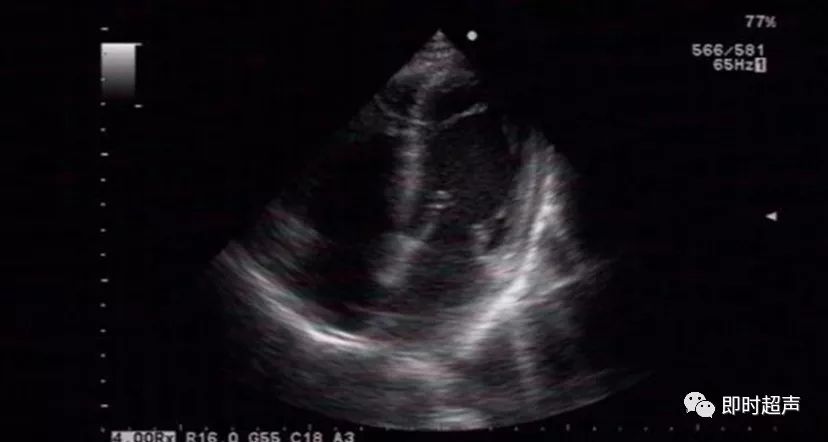

左室假腱索(lvft)图2

jk病例左室假腱索